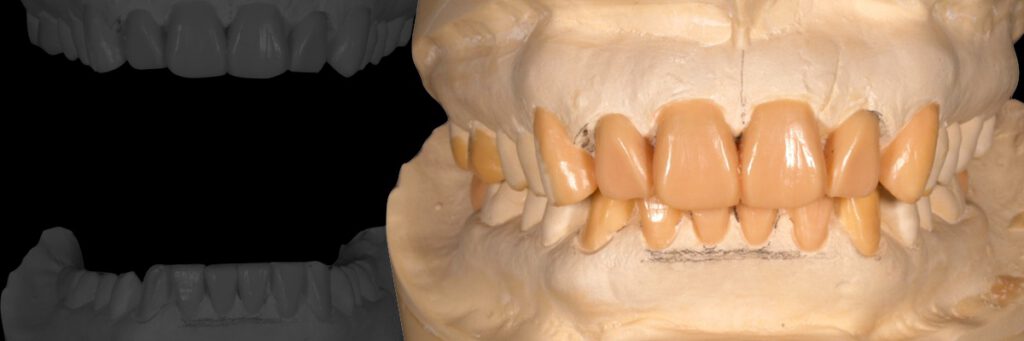

Diagnostic Wax-up

インプラント治療は、診査・診断・治療計画が全てです。フリーハンドでインプラントを埋入するのではなく、3Dシミュレーションを行い、計画的に間違いの起こらないよう埋入することが肝心です。

優れたインプラントクリニックは、歯科技工士を大切にします。歯科医師と技工士のチームワークが成り立って初めて高品質のインプラント治療が可能になります。目に見えている人工歯は技工士の作品なのです。